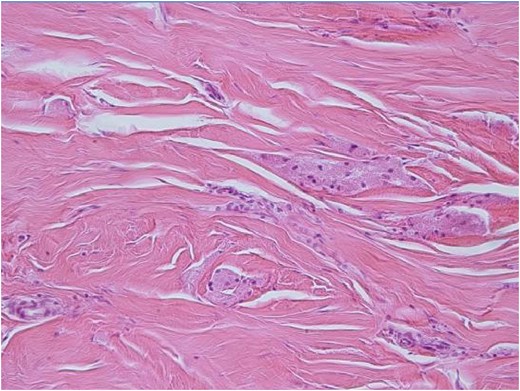

H-E ×200: On medium power examination tumor cells are separated by fine sclerotic collagenous tissue.

Microscopically, the tumor was poorly circumscribed and diffusely infiltrating. Neoplastic cells were large, polygonal with eosinophilic granular cytoplasm and small round to ovoid nuclei. They were separated by sclerotic collagenous tissue (Fig. 5). Few mitotic figures were noticed. Atypia, spindling, high nuclear to cytoplasmic ratio, pleomorphism or areas of necrosis were not identified.

Immunohistochemical study was positive for S-100, CD-68, Inhibin-A, Calretinin, CD-57, NSE and negative for AE-1/AE-3 and Desmin. Ki-67 showed positivity in less than 1% of tumor cells. The tumor was diagnosed as morphologically and immunohistochemically consistent with granular cell tumor.